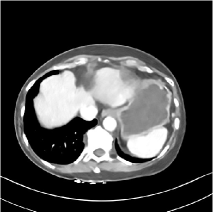

Refer to caption WavResNet [11]Refer to caption WavResNet [11]Refer to caption WavResNet [11]Refer to caption Momentum-Net (SimpleCNN)Refer to caption Momentum-Net (SimpleCNN)Refer to caption Momentum-Net (SimpleCNN)Refer to caption Momentum-Net (SimpleCNN-RSN)Refer to caption Momentum-Net (SimpleCNN-RSN)Refer to caption Momentum-Net (SimpleCNN-RSN)Refer to caption Momentum-Net (Dn-RSN)Refer to caption Momentum-Net (Dn-RSN)Refer to caption Momentum-Net (Dn-RSN)Refer to caption ReferenceRefer to caption ReferenceRefer to caption Reference

Refer to caption Refer to caption Refer to caption Refer to caption Refer to caption Refer to caption Refer to caption Refer to caption Refer to caption Refer to caption Refer to caption Refer to caption Refer to caption Refer to caption Refer to caption

Fig. 3: Three examples (from top to bottom) of the reconstructed testing images using Momentum-Net with SimpleCNN (the second column), with SimpleCNN-RSN (the third column), and with Dn-RSN (the fourth column). The compared WavResNet denoised images are shown in the first column, and the reference images are in the fifth column. See their FBP images in Fig. 4.

3.2 Proposed Momentum-Net with SimpleCNN

Fig. 2 shows that the proposed Momentum-Net with SimpleCNN decreases RMSE dramatically in the first 30 layers, and tends to converge in 50 layers. The Momentum-Net reduces the mean RMSE value by 4.5 HU and gives smaller standard deviations in RMSE, compared to WavResNet, as reported in Table 1. This implies that the proposed Momentum-Net with SimpleCNN can improve both the accuracy and stability of low-dose CT image reconstruction than a state-of-the-art image denoising deep NN, WavResNet. The proposed Momentum-Net with SimpleCNN better removes noise and streak artifacts than WavResNet. It also provides clearer reconstructions of some details; see, in Fig. 3, the boundaries shown in the zoomed region at the top-right corner in the first example, the arrow pointed structures in zoomed areas of the second example, and the arrow pointed tissues in the left zoomed region in the third example.

3.3 Momentum-Nets involving RSN-based training

We show the reconstructed examples by Momentum-Net with SimpleCNN-RSN and Dn-RSN in the third and fourth columns of Fig. 3 respectively. Comparing the first three and the last columns in Fig. 3, we observe that Momentum-Net with SimpleCNN-RSN provides generally noisier reconstructions than WavResNet and Momentum-Net with SimpleCNN. However, Momentum-Net with SimpleCNN-RSN sometimes can provide clearer details than WavResNet. For example, in the right zoomed box of the second example, Momentum-Net with SimpleCNN-RSN shows better reconstruction quality for the arrow pointed structures than WavResNet, and in the left zoomed box in the third row, the former gives clearer small tissues marked by red arrows than the latter. Table 1 reports that Momentum-Net with SimpleCNN-RSN is approximately 2.9 RMSE (HU) higher than WavResNet, while it has smaller standard deviations. This implies that Momentum-Net with SimpleCNN-RSN is more stable than WavResNet, although it may not provide better image qualities. Momentum-Net with Dn-RSN, however, provides the worst visual and numerical results among the compared four methods in this paper.